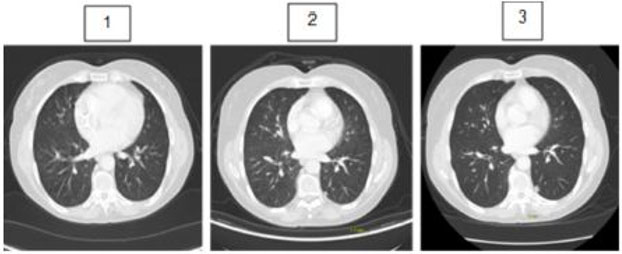

Two years after completion of concurrent chemotherapy and radiation therapy, PET/CT scans revealed a 0.5 cm left lower lobe sub-pleural nodule with SUV max 1.1 (without significant tracer uptake). She remained asymptomatic with no nausea, vomiting, altered bowel habits or change in appetite or weight. Short interval CT chest was recommended and performed three months later. It showed a significant increase in size of the nodule from 0.5 to 0.7 cm suggesting malignant potential (Figure 5). The differential diagnoses included early primary lung cancer or an isolated metastatic lesion. The case was discussed at thoracic cancer conference and a multidisciplinary decision was made for definitive surgery up front.

Figure 5: (1) Sequential CT images through the chest demonstrating development of new 5 mm non-FDG avid left lower lobe nodule (2) and interval enlargement to 7 mm on (3) concerning for metastatic disease.